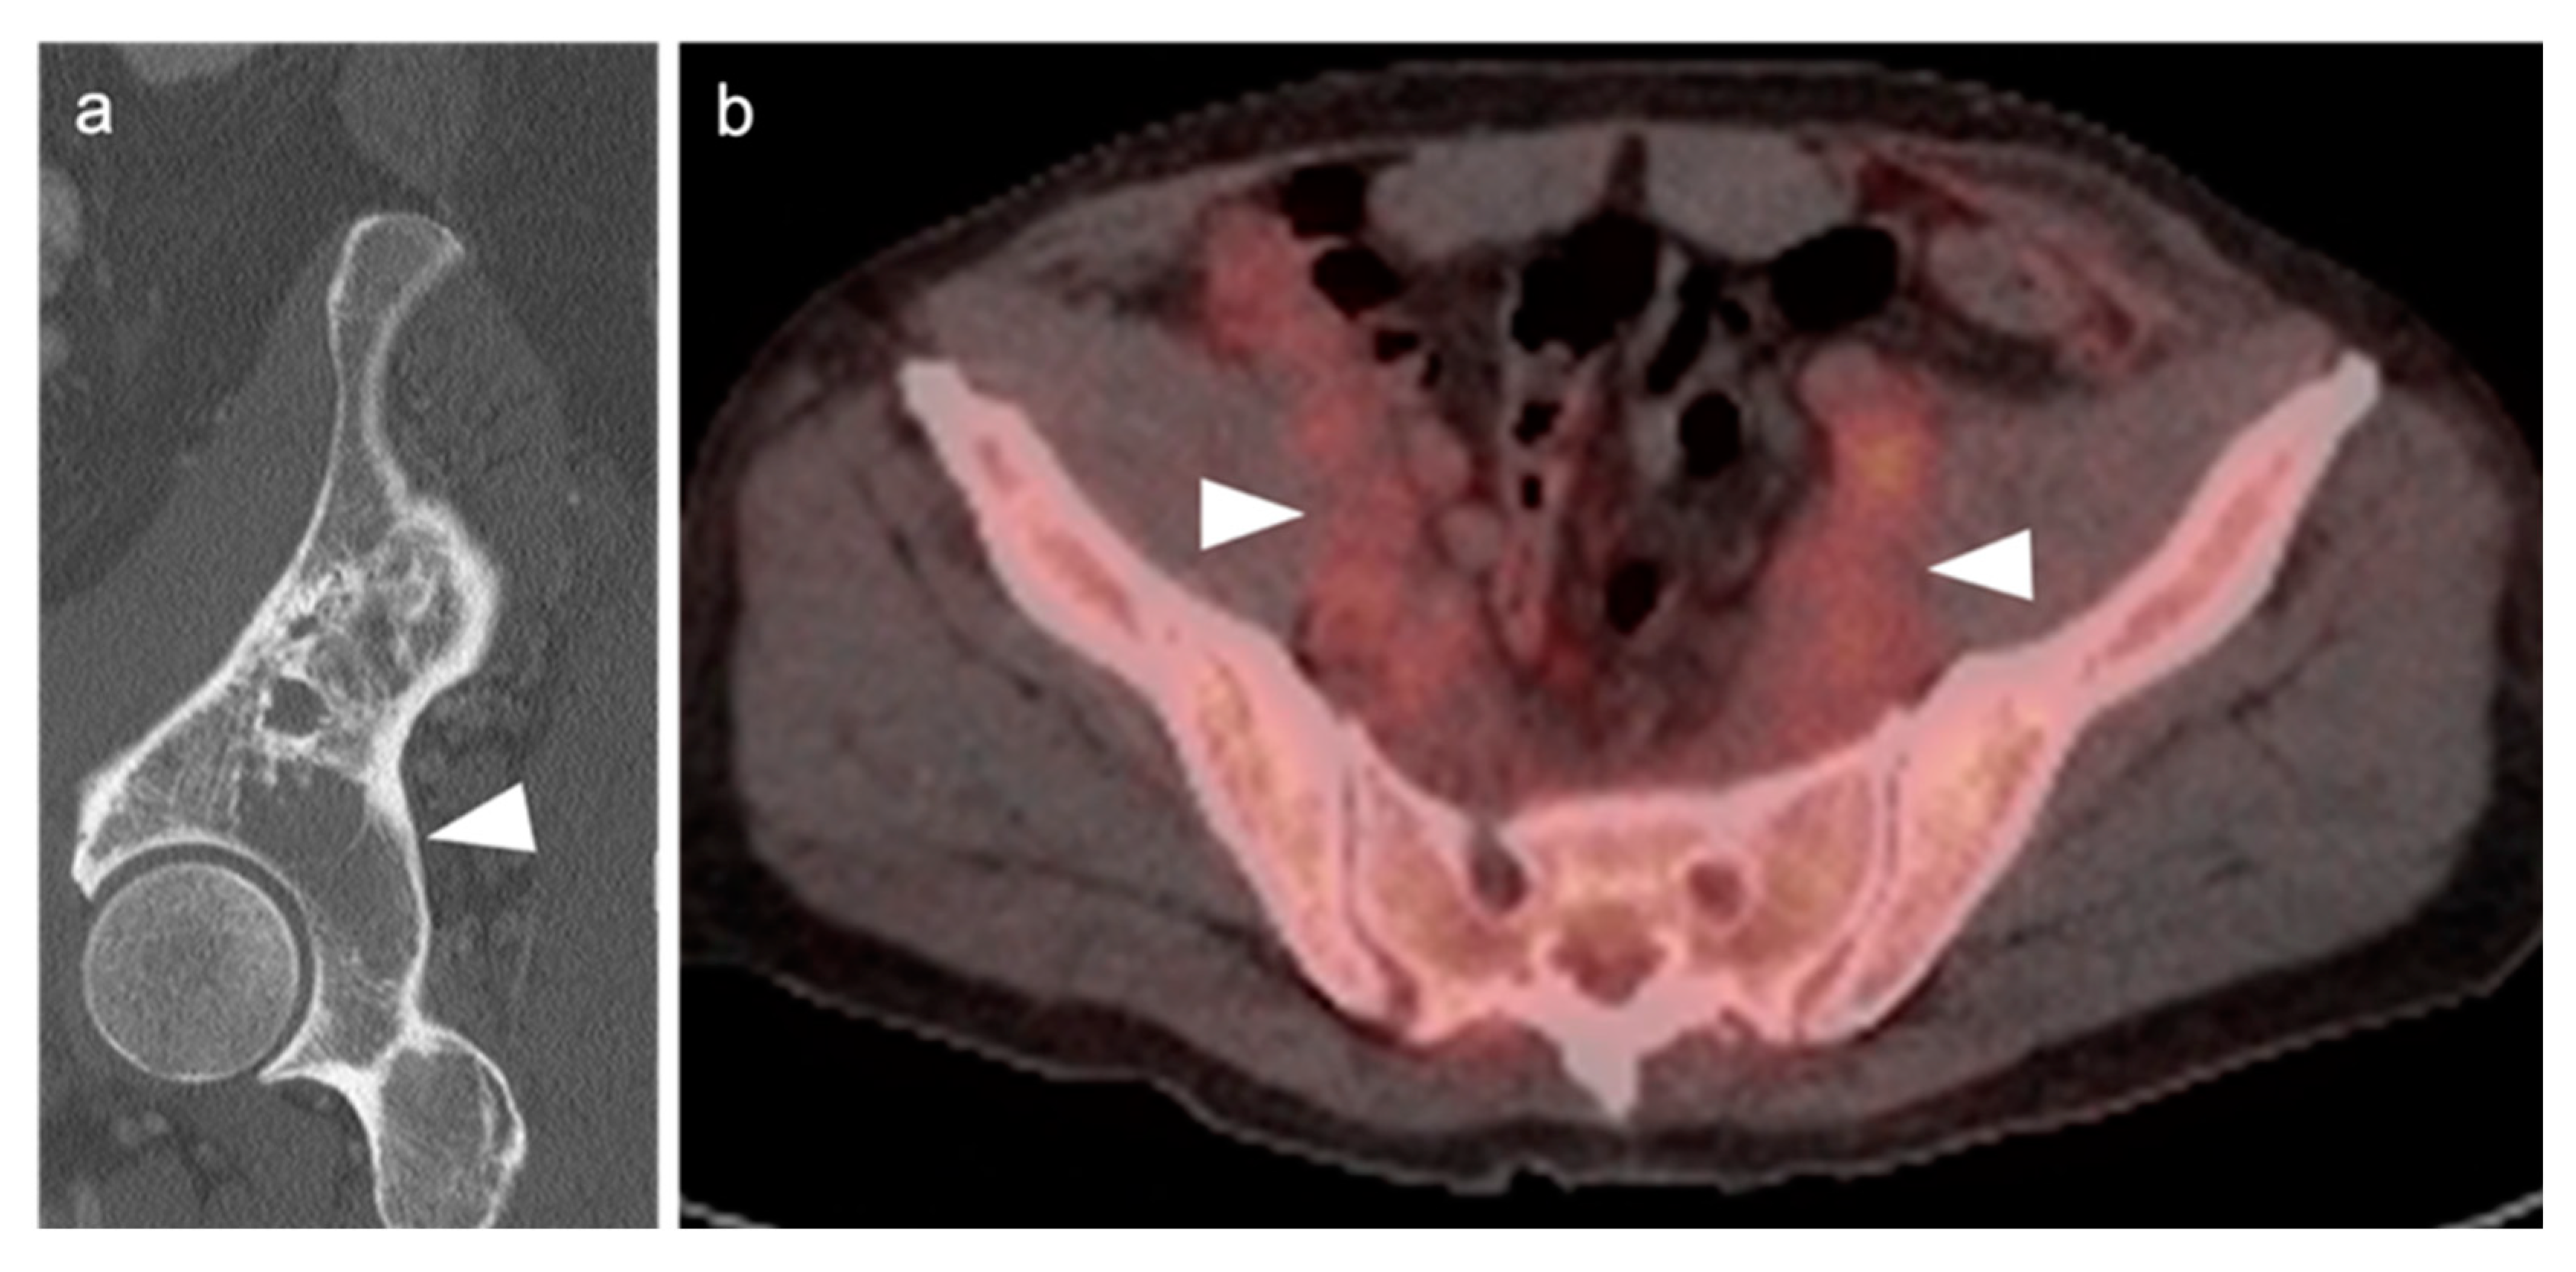

2.2.3. Baseline FDG PET-CT for Staging Lymphoma

2.3.6. Multiple Myeloma (MM)

- Kashyap, R.; Rai Mittal, B.; Manohar, K.; Balasubramanian Harisankar, C.N.; Bhattacharya, A.; Singh, B.; Malhotra, P.; Varma, S. Extranodal manifestations of lymphoma on [¹⁸F]FDG-PET/CT: A pictorial essay. Cancer Imaging 2011, 11, 166–174. [Google Scholar] [CrossRef]